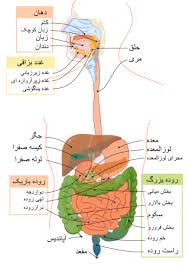

قیمت: 52٬000 تومان - دسته بندی فایل: پاورپوینتپاورپوینت پانکراس

فروش ویژه پاوزپوینت حرفه ای پانکراس با تخفیف استثنایی قیمت 63 هزار تومان تعداد اسلاید: 30 اسلاید